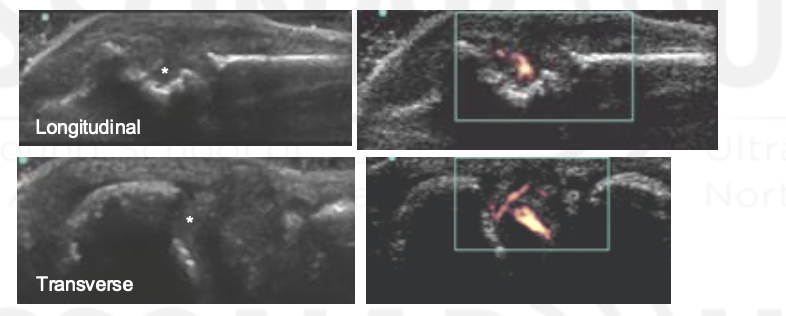

Grade The Synovial Hypertrophy

Grade this

B: grade 1 (up to 3 single signals — 1 confluent + 2 single — 2 confluent)

Minimal synovial hypertrophy up to the imaginary horizontal line connecting 2 joints; Power Doppler up to 3 single signals — 1 confluent + 2 single — 2 confluent

Grade 1: minimal

Moderate synovial hypertrophy protruding over the joint line along with concave surface; Larger than grade 1 but <50% of synovial hypertrophy covered by signals

Grade 2: moderate

Severe synovial hypertrophy producing beyond the joint line with convex surface; more than 50% of SH area covered by signals

Grade 3: Severe

Grade this doppler

Grade 2: Larger than grade 1 + <50% of SH area

Grade 3: >50% of the synovial hypertrophy is covered by signals